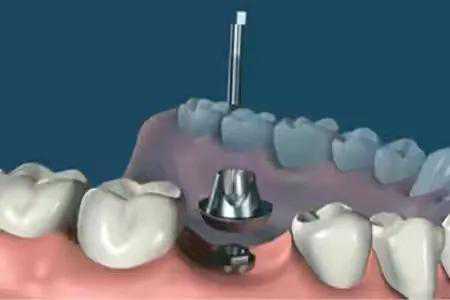

step4.

安装愈合基台,使种植体穿出牙龈,等待软组织成形。

step5.

在差不多2--3周后,软组织成形后。种植牙医生会用永久基台换下愈合基台。